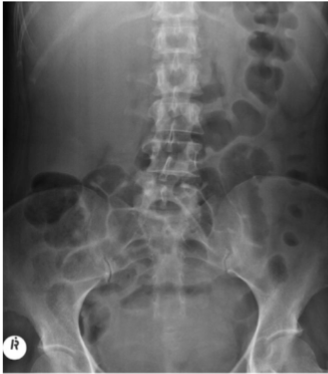

What is this and what type of scan

chronic constipation, abx